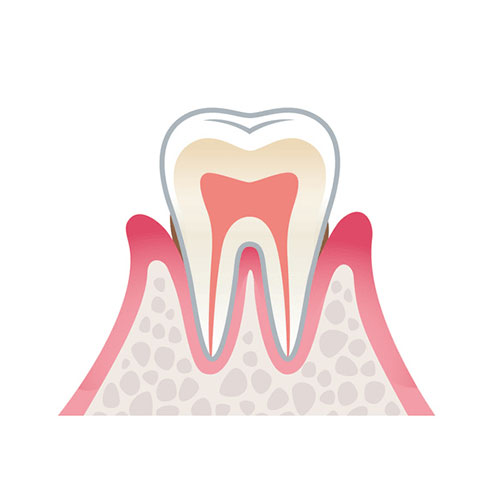

歯周病とは歯と歯茎のすき間(歯周ポケット)から細菌が侵入し、歯肉に炎症を引き起こしたり、歯を支える骨(歯槽骨)などが溶けたりする病気です。

健康な状態

薄いピンク色の歯肉で、歯と歯肉のすき間(歯周ポケット)がなく引き締まっています。ブラッシング時に出血しません。